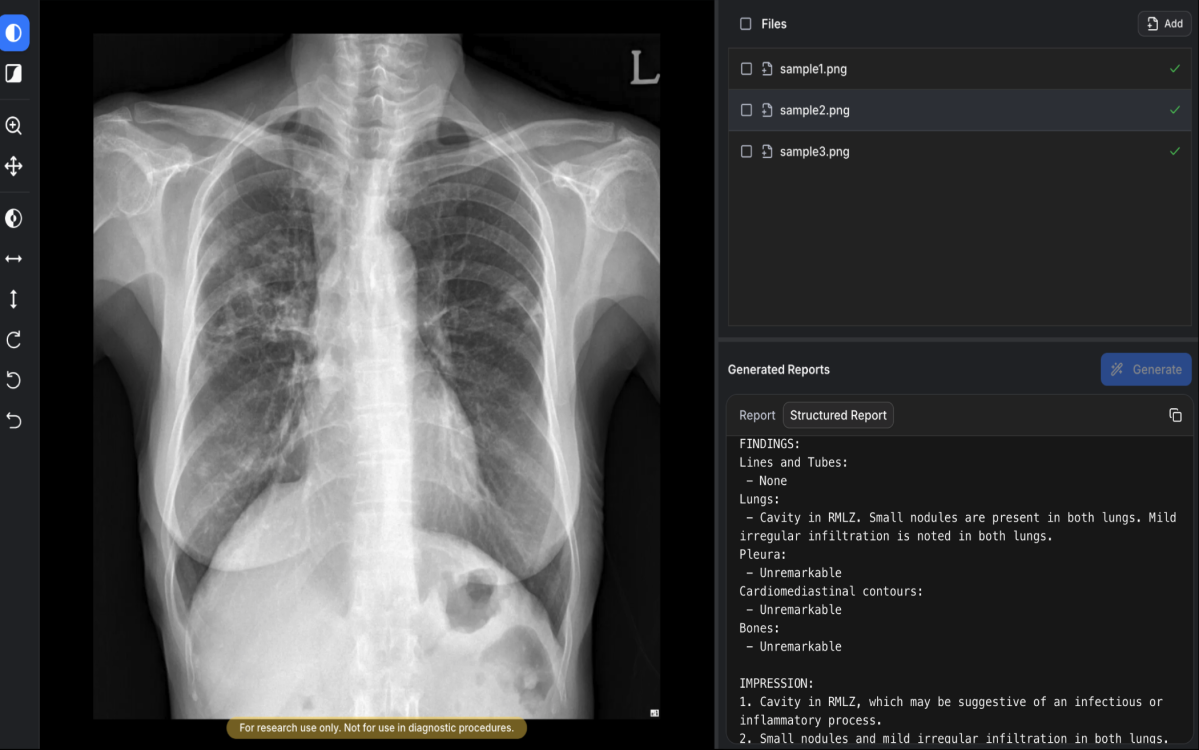

¼ûºøAI°¡ ÀÚ»çÀÇ ÈäºÎX¼± ¿¹ºñ¼Ò°ß¼ »ý¼º ¼Ö·ç¼Ç ¡®¿¡¾î¸®µå-¾¾¿¢½º¾Ë(AIRead-CXR)¡¯¿¡ ´ëÇØ ´ëÇѹα¹ ½ÄǰÀǾàǰ¾ÈÀüó(MFDS) 3µî±Þ ÀÎÇã°¡¸¦ ȹµæÇß´Ù°í 2ÀÏ ¹àÇû´Ù.

AIRead-CXRÀº ÀǷ῵»ó ºÐ¾ß¿¡¼ ¼¼°è ÃÖÃÊ·Î »ý¼ºÇü AI ±â¹Ý ¼ÒÇÁÆ®¿þ¾î ÀÇ·á±â±â(SaMD)·Î ½Ä¾àó Çã°¡¸¦ ¹ÞÀº Á¦Ç°ÀÌ´Ù. ±âÁ¸¿¡ À¯·´¿¡¼ »ý¼ºÇü AI ±â¹Ý ÀÇ·á±â±â°¡ Á¸ÀçÇÏÁö¸¸ ÀǷ῵»óÀ» Á÷Á¢ ºÐ¼®ÇØ ¿¹ºñ¼Ò°ß¼¸¦ »ý¼ºÇÏ´Â ´Üµ¶ Á¦Ç°À¸·Î´Â À̹ø ½ÂÀÎÀÌ ¼¼°è ÃÖÃʶó´Â Á¡¿¡¼ Àǹ̰¡ Å©´Ù.

½Ä¾àó´Â Àü¹®ÀÇ ÆÇµ¶¹®°ú AI ÃÊ¾È °£ ºñ±³ Æò°¡¸¦ ÅëÇØ À¯È¿¼º°ú ¾ÈÀü¼ºÀ» È®ÀÎÇßÀ¸¸ç ÀÓ»óÀº ¼¿ï´ëº´¿ø°ú ºÐ´ç¼¿ï´ëº´¿ø¿¡¼ 1000°Ç ÀÌ»óÀÇ ÈäºÎ X¼± µ¥ÀÌÅ͸¦ ±â¹ÝÀ¸·Î È®Áõ ´Ü°è±îÁö ÁøÇàµÆ´Ù.

AIRead-CXRÀº ±¹³»¿Ü¿¡¼ È®º¸ÇÑ ¾à 1400¸¸°ÇÀÇ µ¥ÀÌÅ͸¦ ÇнÀÇØ ´Ù¾çÇÑ º´¿ø ȯ°æ¿¡¼ ÃÔ¿µµÈ PA ¶Ç´Â AP ÈäºÎX¼±¿¡ ´ëÇØ ¾ÈÁ¤ÀûÀ¸·Î ¿¹ºñ¼Ò°ß¼¸¦ Á¦°øÇÑ´Ù. ÇÙ½ÉÀûÀ¸·Î °ËÁõµÈ 57°³ ¼Ò°ß ¹× Áúȯ¿¡ ´ëÇØ ÆÇµ¶º¸Á¶ ¼º´ÉÀ» Á¦°øÇÒ »Ó ¾Æ´Ï¶ó ÀÌ¿ÜÀÇ ´Ù¾çÇÑ ¿µ»ó ¼Ò°ßµµ ÇØ¼®¡¤¾ð±ÞÇÒ ¼ö ÀÖ´Ù. ½ÇÁ¦ ÀÓ»ó ÇöÀåÀÇ ¿öÅ©Ç÷ο츦 ¹Ý¿µÇØ ÀÇ·áÁøÀÌ º¸´Ù È¿À²ÀûÀ¸·Î ÆÇµ¶ ¾÷¹«¸¦ ¼öÇàÇÒ ¼ö ÀÖµµ·Ï ¼³°èµÆ´Ù.

ǰÁú °æÀï·Âµµ ÁÖ¸ñµÈ´Ù. °ø°³µÈ ÀÓ»ó ³í¹®¿¡ µû¸£¸é ÈäºÎ ¿µ»ó Àü¹®ÀǵéÀÌ Æò°¡ÇÑ AI ¿¹ºñ¼Ò°ß¼ Æò±Õ ¼ö¿ëµµ´Â 85%·Î, ºñ±³ ´ë»óÀÎ MedGemma(66.9%)¸¦ »óȸÇß´Ù. »ý¼ºÇü AIÀÇ ´ëÇ¥Àû ÇѰèÀΠȯ°¢ ºñÀ² ¿ª½Ã 0.3%·Î MedGemma(9.7%) ´ëºñ ¾ÈÁ¤¼ºÀ» º¸¿´´Ù. ¼ûºøAI´Â Á¦Ç° ¿Ï¼ºµµ¸¦ ³ôÀ̱â À§ÇØ Áö³ 2³â°£ ±Û·Î¹ú À¥µ¥¸ð ¡®AIRead-CXR¡¯¸¦ Àü¹®ÀÇ ´ë»óÀ¸·Î ¿î¿µÇÏ¸ç »ç¿ëÀÚ Çǵå¹éÀ» Áö¼ÓÇØ¼ ¹Ý¿µÇØ ¿Ô´Ù.

¹è¿õ ¼ûºøAI ´ëÇ¥´Â ¡°¼¼°è ÃÖÃÊ·Î ÀǷ῵»ó ºÐ¾ßÀÇ »ý¼ºÇü AI ±â¹Ý SaMD ½ÂÀÎÀ» ¹Þ°Ô µÇ¾î ¿µ±¤½º·´´Ù¡±¶ó¸ç ¡°AIRead-CXRÀÌ ÈäºÎX¼±À¸·Î ÀÎÇÑ º´¡¤ÀÇ¿ø ¹× ¿µ»óÀÇÇаú Àü¹®ÀǵéÀÇ ¾÷¹« ºÎ´ãÀ» ´ú°í °Ç°ÇÑ ¼¼»óÀ» ¸¸µå´Â µ¥ ±â¿©ÇÏ´Â Á¦Ç°À¸·Î ÀÚ¸®¸Å±èÇÏ±æ ±â´ëÇÑ´Ù¡±°í ¸»Çß´Ù.